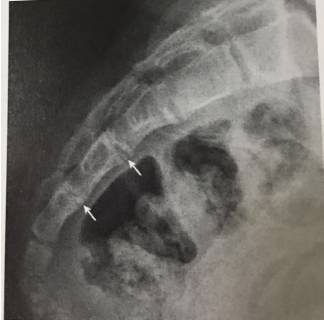

12、齿状突终末小骨

终末小骨位于齿状突尖部“V”形裂隙内,易误认为是碎骨片。

13、寰椎后弓旁正中央裂

寰椎后弓旁中央裂为正常变异,易误为骨折。